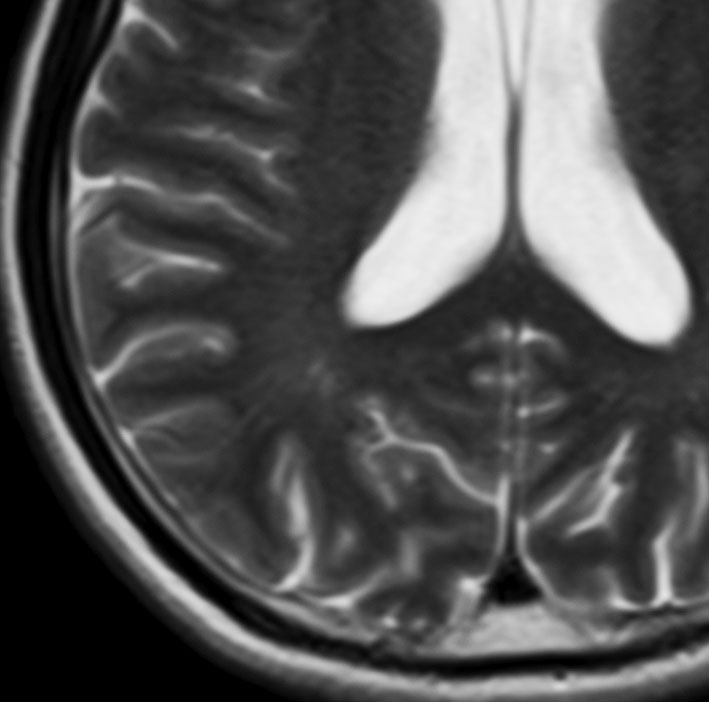

ND-LCH (neurodegenerative LCH) ガドリニウム増強されないタイプ

- 脳のLCHですが,広範囲な病変で,ガドリニウムで白い造影像がでません

- 脳炎のような臨床像です

- T2強調画像の不規則な高信号領域が,両側の小脳白質,大脳基底核,橋,大脳深部白質に生じます

- LCHを有する子どもの20%くらいに画像上の脳病変が生じますが,その内の症候性のものを言います

- 変性性神経疾患のような多発性脳病変と症状を出すものです

- 症状は急激に悪くなることがあります

- 小脳失調,振戦,構語障害,嚥下障害,人格変化,学習障害,知能障害,行動異常,認知障害,精神発達遅滞などを生じます

- 病変が広いと様々な神経精神症状を残してしまいます

- 脳のLCHの代表的な症状が尿崩症なのですが,尿崩症が判明してからND-LCHの症状が出ることが多いです

- 水頭症を合併することがあります